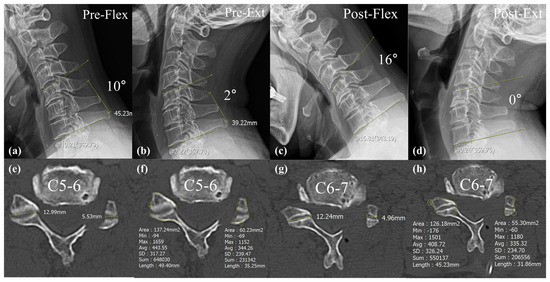

| ROM Segmental Angle | 17.1 ± 8.4 | 18.2 ± 10.2 | 0.52 |

| ROM Segmental Angle | 5.2 ± 5.5 | 9.2 ± 6.3 | 0.01 * |

| ROM Segmental Angle | 6.2 ± 5.6 | 15.2 ± 7.5 | <0.01 * |

| Foraminal dimension (mm2) | 34.3 ± 8.5 | 31.5 ± 7.8 | 0.16 |

| Post foraminal dimension (mm2) | 54.5 ± 8.2 | 53.3 ± 7.4 | 0.51 |

| Foraminal enlargement (%) | 63.8 ± 26.1 | 75.5 ± 34.6 | 0.13 |